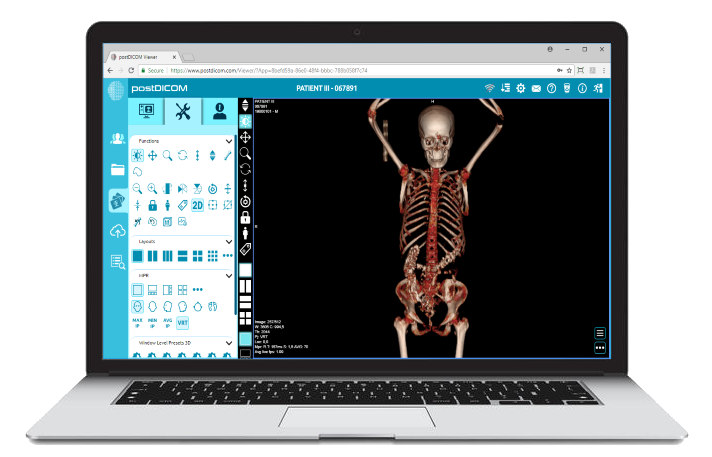

PostDICOM’s cloud-based imaging platform is structured around these modern design principles. Rather than adapting legacy workstation models to web access, the platform is built to support distributed, device-independent workflows from the foundation.

PostDICOM operates on centralized cloud infrastructure, allowing imaging data to be securely stored, managed, and streamed without dependency on local workstation installations.

By centralizing processing and storage, the platform minimizes variability between devices while maintaining consistent user experience across desktops, laptops, tablets, and smartphones.

The viewer operates within standard web browsers, eliminating the need for software installation. This zero-footprint approach enables:

Imaging studies are streamed securely via encrypted HTTPS communication. Access is governed by role-based permissions, ensuring that users only view authorized studies.

Because rendering occurs within a controlled browser session, images are not permanently stored on endpoint devices, reducing data exposure risk.